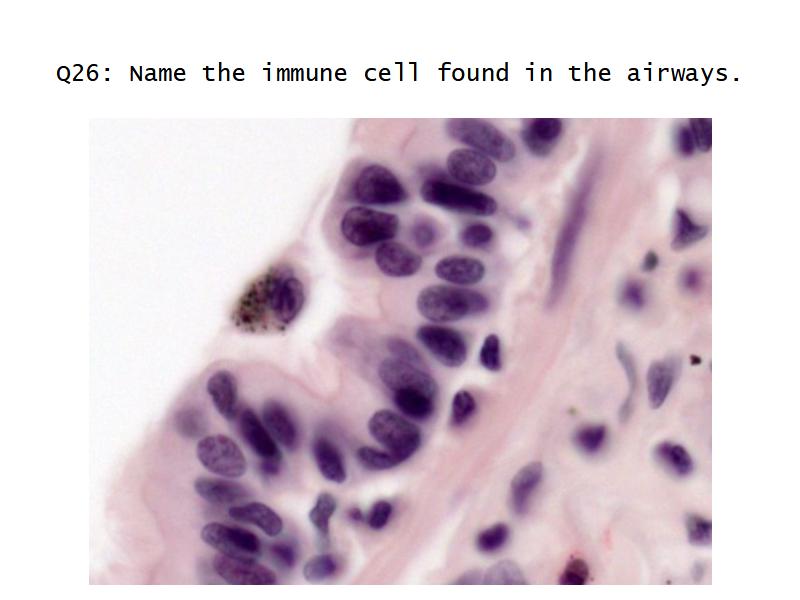

Slides: Respiratory System

- Slide 71: Nostril

- Slide 72 & 74: Lung

- Slide 73: Trachea

- Slide 108: Olfactory epithelium

- Slide 111: Epiglottis

Respiratory epithelium

- Pseudostratified

- Ciliated

- Columnar

- Epithelium with

- 4 Cells

- Ciliated columnar cells

- Non-ciliated columnar cells

- Goblet cells

- Basal cells